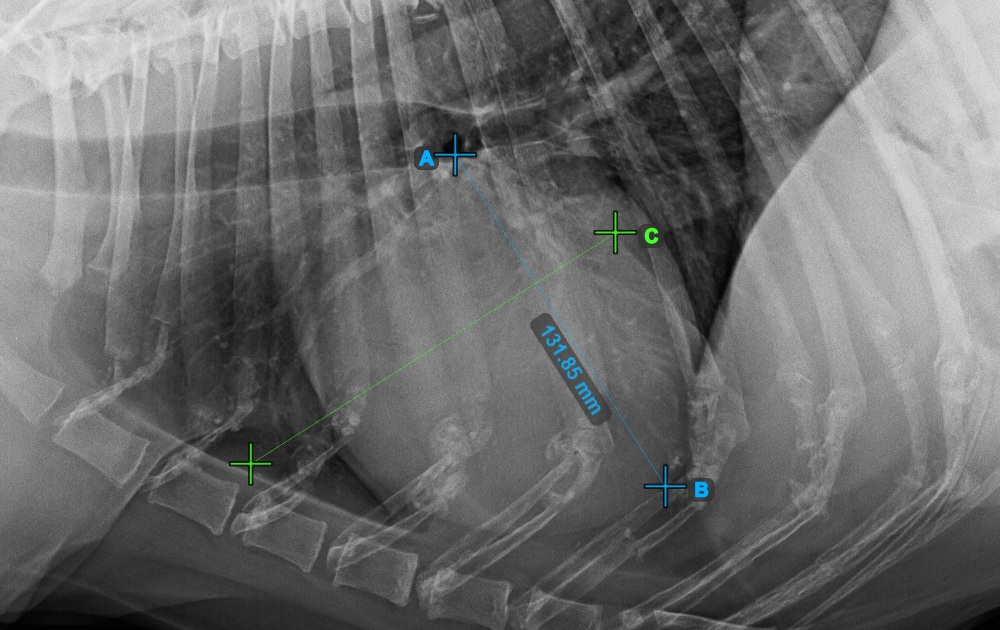

Fahren Sie mit der Messung fort, indem Sie den breitesten rechten (vorderen) Punkt der Kurzachse des Herzens markieren.

Das Bild unten zeigt die typische Platzierung des vordersten Punkts auf der Kurzachse des Herzens.